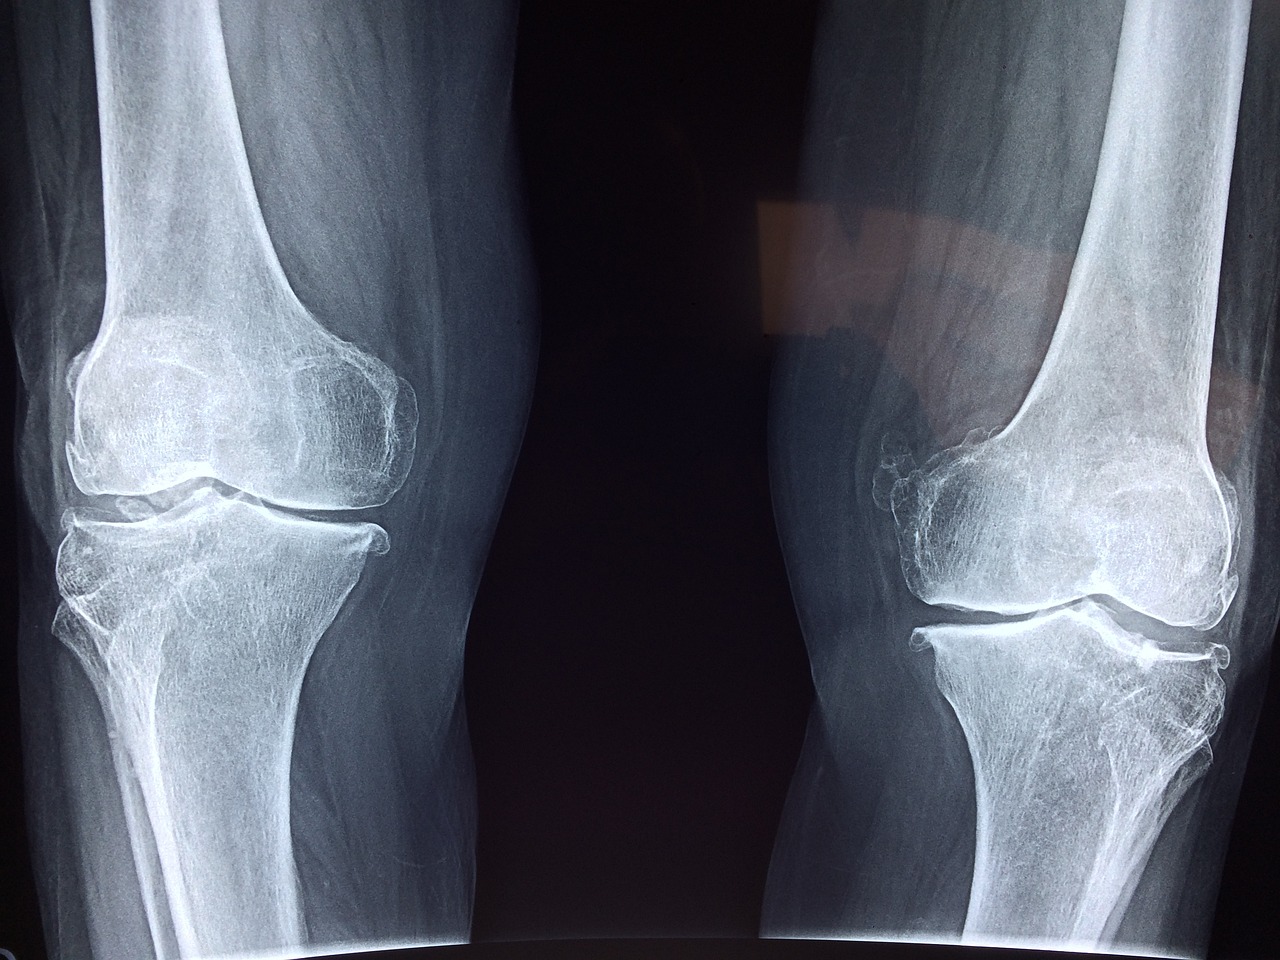

4. 진단

퇴행성 관절염은 환자의 증상, 검사 결과, X-선 및 기타 영상 촬영을 통해 진단됩니다. 의사는 증상의 정도와 환자의 건강 상태를 고려하여 진단을 수립합니다.